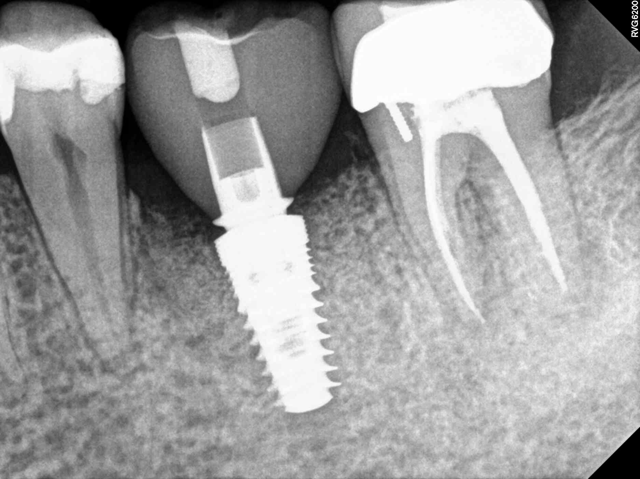

Make sure the scan post is fully seated on the implant and verify with an X-ray. (Fig. 2).

For a screw-retained crown, it is best to place the scan post notch interproximally because the sprue will mill 90 degrees from the notch. For an abutment, notch position is not an issue because the software will position it using different criteria.

Make sure scan body is correctly seated over notch of scan post.

The shiny scan post may be difficult to scan. Focus on scanning the area where the scan post meets the gingiva. If you do not have enough scanned data, the software may assume the scan post is an artifact and remove it from the image.

Before dismissing the patient, always move forward to making the models step to confirm that all imaging is accurate.